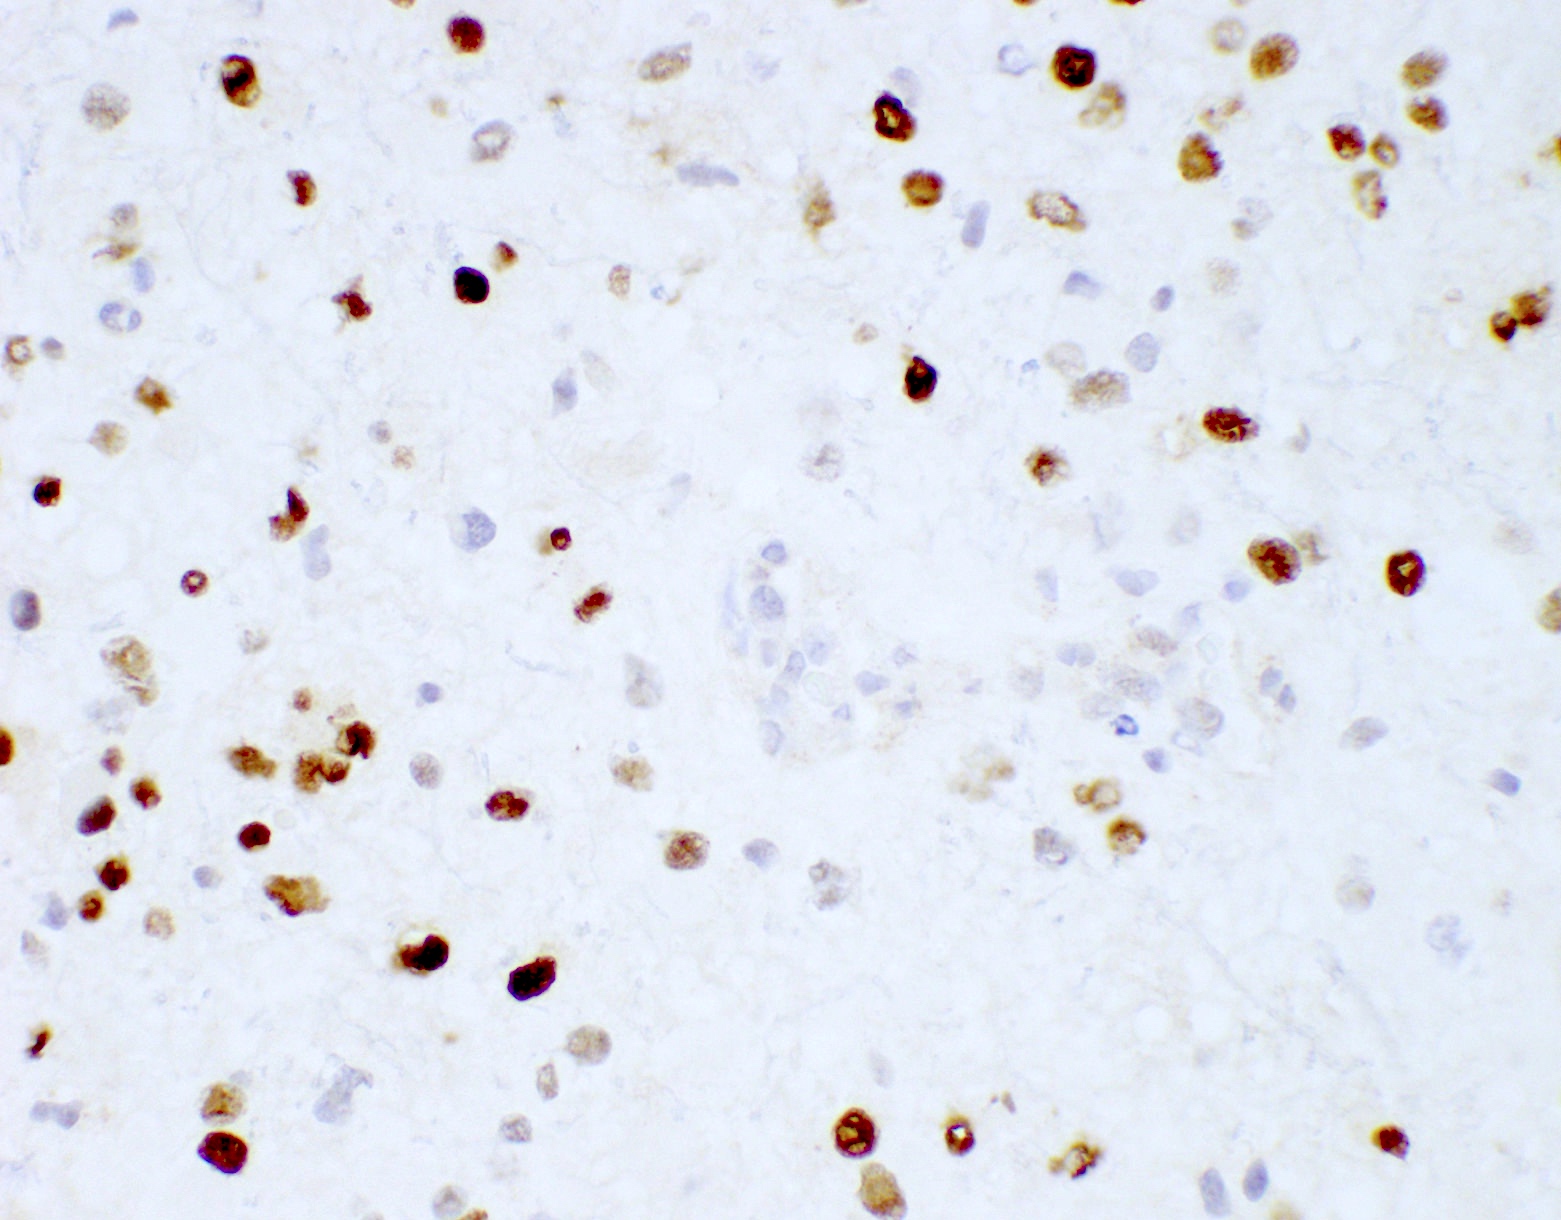

Positive stains

Negative stains

- ATRX

- Loss of nuclear ATRX is typical of diffuse astrocytomas, not oligodendrogliomas or reactive gliosis (Front Oncol 2017;7:236)

- Strong nuclear expression in nonneoplastic vasculature and cells serves as an internal control

- p53 mutation and ATRX promoter mutation nearly always present (typically absent in oligodendroglioma, IDH mutant and 1p19q codeleted) (N Engl J Med 2015;372:2481)

- ATRX: nuclear expression lost (consistent with mutant)